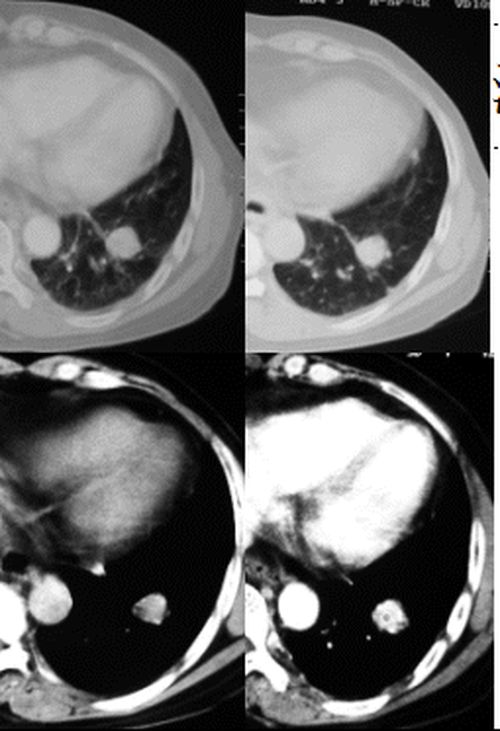

(1)发生部位:炎性假瘤可发生在两肺的任何部位,但多位于肺的表浅部位,邻近胸膜处或者靠近叶间裂。可以跨叶生长,原因可能是跨叶浸润的炎症使得假瘤跨叶融合的结果。

(5)假瘤边缘:

①有假无假性包膜者边缘清楚。有的由于肿块不规则可表现分叶状。

② 无假性包膜者,假瘤周围有纤维化和多种细胞成分侵润,表现为片状、边缘模糊的团块状影。或有轻度的渗出性病变,边缘模糊,以组织细胞围增生型多见。有的假瘤周围还可以出现类似周围型肺癌的放射冠状表现。

(6)邻近改变:位于肺周边部的假瘤,其邻近胸膜可见局限性粘连增厚。位于近肺门区的假瘤,偶可阻塞支气管,形成肺叶不张而将假瘤包裹,甚似中央性肺癌,但不出现肺门或纵膈淋巴结肿大。

②病灶可有垂直于胸膜的刀切样边缘;

③胸膜局部增厚粘连,无胸水及胸膜钙化,病灶与胸壁间有浅淡条状低密度影;

④孤立圆形类圆形影多邻近胸膜;密度较均匀,边缘光滑,可有粗长的毛刺或呈锯齿状;

⑤肺门及纵隔内无肿大的淋巴结。